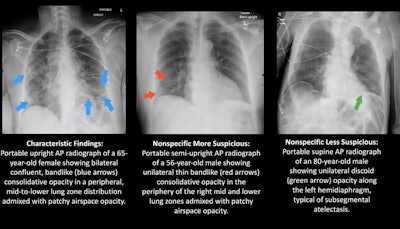

Two board-certified radiologists who were blinded to the RT-PCR results assessed each of the 60 chest x-rays in consensus and classified the images into one of three patterns: characteristic for COVID-19, nonspecific for COVID-19, and negative. The nonspecific patterns were further broken down into "more suspicious" or "less suspicious" for COVID-19, Igi explained.

Image courtesy of Dr. Mae Igi."COVID-19-positive patients over 50 show earlier, more characteristic patterns of statistically significant [chest x-ray] changes than younger patients, suggesting that [chest x-ray] is useful in the early diagnosis of the disease," Igi concluded.

What are characteristic findings on chest x-ray that are telltale signs of COVID-19? They can include the presence of bilateral patchy or confluent bandlike ground-glass opacity, or consolidation in a peripheral or middle to lower lung zone.

On the other hand, abnormal findings that are less suspicious for COVID-19 can include pulmonary edema, atelectasis, and interstitial changes.